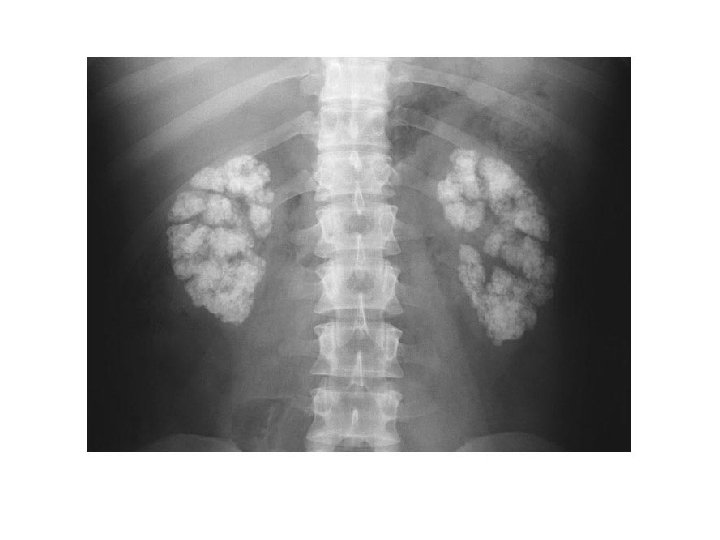

DMSA • IV injection – bound to proximal tubules • Indications: – Assessment of kidneys in acute phase of UTI (acute pyelonephritis) – Assessment of kidneys in late phase of UTI – detection of scar – Assessment of horseshoe, solitary or ectopic kidney – Localisation of poor or very poorly functioning kidney – Assessment of renal function in the presence of an abdominal mass BNMS guidelines

Cortical scintigraphy • Scintigraphy with 99 m. Tc-dimercaptosuccinic acid (DMSA) – simple and non-invasive – Static imaging 2 -4 hours after iv injection – Delayed or post-frusemide images in hydronephrosis • The sensitivity of 99 m. Tc-DMSA for the detection of parenchymal defects due to infection - from 80% to 100% – does not allow differentiation of acute pyelonephritis from renal scars

Cortical scintigraphy • Abnormal findings on cortical scintigraphy are found in 52%– 78% of children during acute pyelonephritis, and the risk that a renal scar will develop can reach 60% • The role of cortical scintigraphy is still largely debated in acute pyelonephritis but is widely accepted in the detection of renal scars • 99 m. Tc-DMSA scintigraphy is the reference method for detecting renal sequelae after UTI, is more sensitive than sonography, and should be performed no sooner than 6 mo after the last documented UTI • Also used to detect scars in VUR